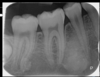

maxillary occlusal

lateral obliques